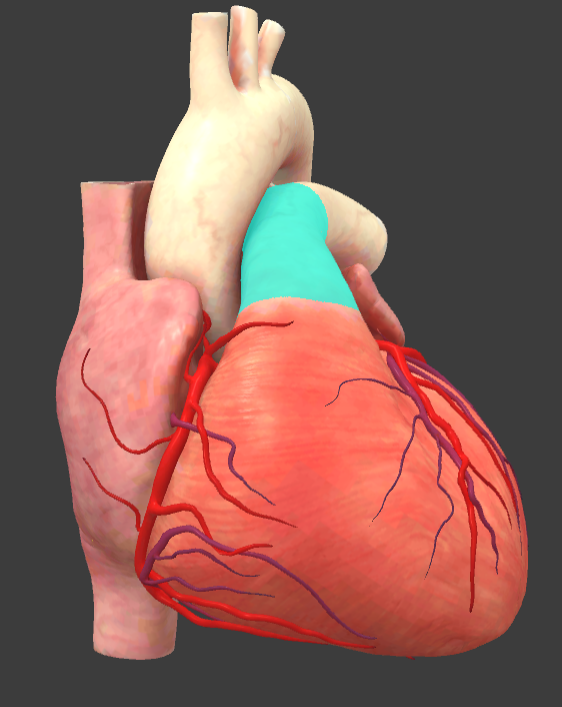

Arch of aorta

Brachiocephalic trunk

Pulmonary trunk

Superior vena cava

Ascending aorta